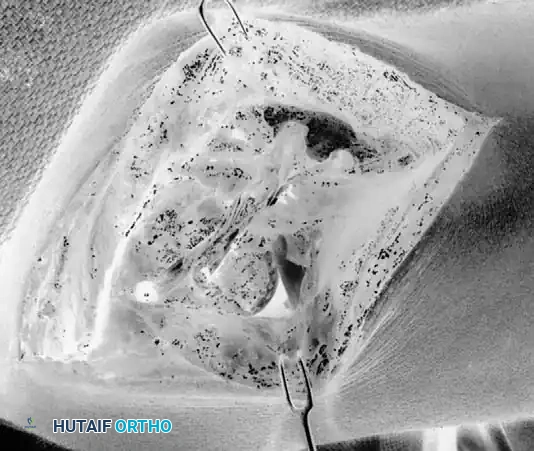

3. Exposure of the UCL:

The flexor-pronator mass is split longitudinally in line with its fibers (often between the two heads of the flexor carpi ulnaris) to expose the native UCL. The native ligament is incised longitudinally to expose the joint and inspect the articular surface.

4. Tunnel Preparation:

Using a high-speed burr or drill, tunnels are created at the anatomic footprints. On the ulna, converging drill holes are made anterior and posterior to the sublime tubercle, leaving a 1 cm bone bridge. On the medial epicondyle, a Y-shaped or docking tunnel is created at the isometric point.

5. Graft Harvesting and Passage:

An autograft is harvested, most commonly the palmaris longus or gracilis tendon. The graft is passed through the ulnar tunnels in a figure-of-eight fashion.